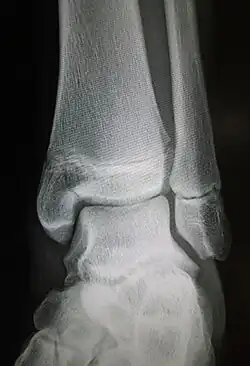

| Radiograph showing a Maisonneuve fracture of the proximal fibula | |

Ankle radiographs are used to detect widening of the tibiofibular syndesmosis or medial clear space. The medial clear space is the area between the talus of the ankle and the medial malleolus. Damage to the deltoid ligament and syndesmotic ligaments result in mortise instability, causing the talus to laterally shift and widen the medial clear space.[4][12] A clinical study, conducted in 2006 and published in the Journal of Bone and Joint Surgery, found that the medial clear space size of a normal ankle and an injured ankle measured at 4 millimetres and 5.4 millimetres in length respectively.[11] To confirm diagnosis, full-leg radiographs are used to inspect for fractures of the proximal fibula and widening of the interosseous clear space (or tibiofibular clear space). The interosseous clear space is the area between the medial side of the fibula and lateral side of the tibia. A peer-reviewed study, published in Injury in 2004, found that an interosseous clear space greater than 10 millimetres indicates diastasis of the syndesmotic ligaments.[4]